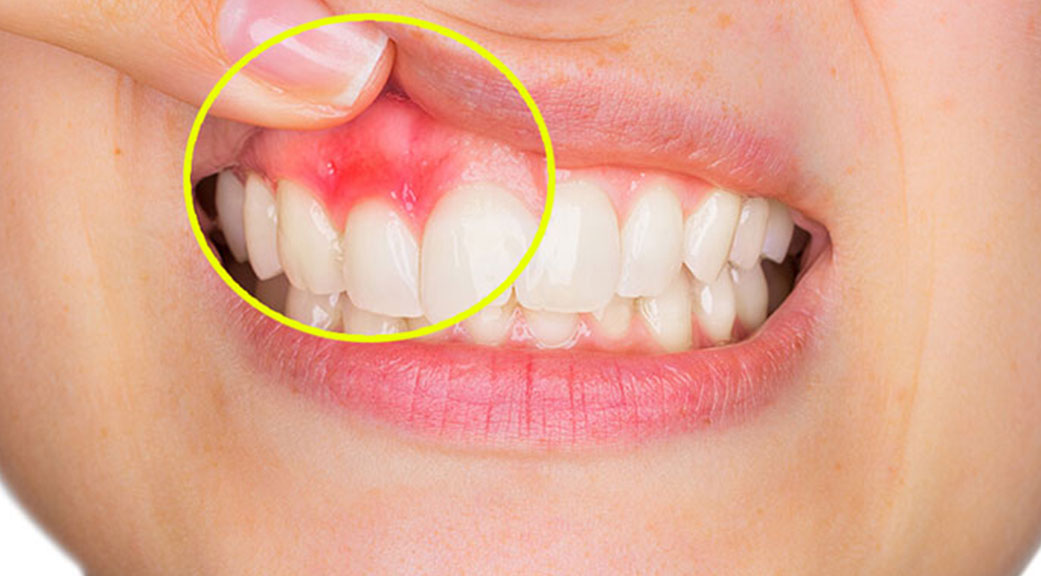

Plaies et infections buccales

Maladies gingivales